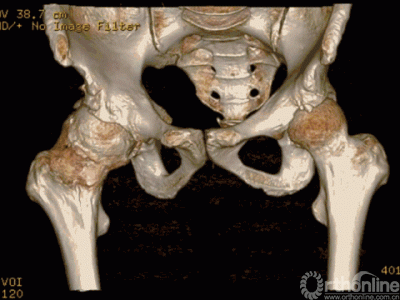

患者术前CT三维重建图像

由AI HIP系统对患者的髋关节CT数据进行人工智能分割与关键点识别,术者可根据智能分割与测量结果综合判断患者情况。如图可见,该患者关节内可见明显畸形。